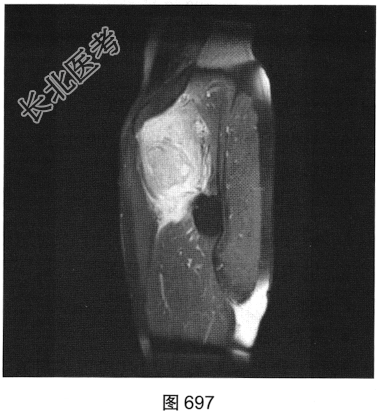

- 多项选择题2.[提示]患者行MRI平扫及增强扫描,见图692~图697。患者MRI平扫及增强扫描图像有哪些阳性表现( )

A、肿块边界不清,信号不均匀

B、肿块周围水肿明显

C、增强扫描肿块呈均匀强化

D、肿块边界清楚,信号均匀

E、增强扫描肿块及周围软组织呈明显不均匀强化

F、与邻近肌肉相比,T1WI呈等信号;T2压脂序列呈明显高信号